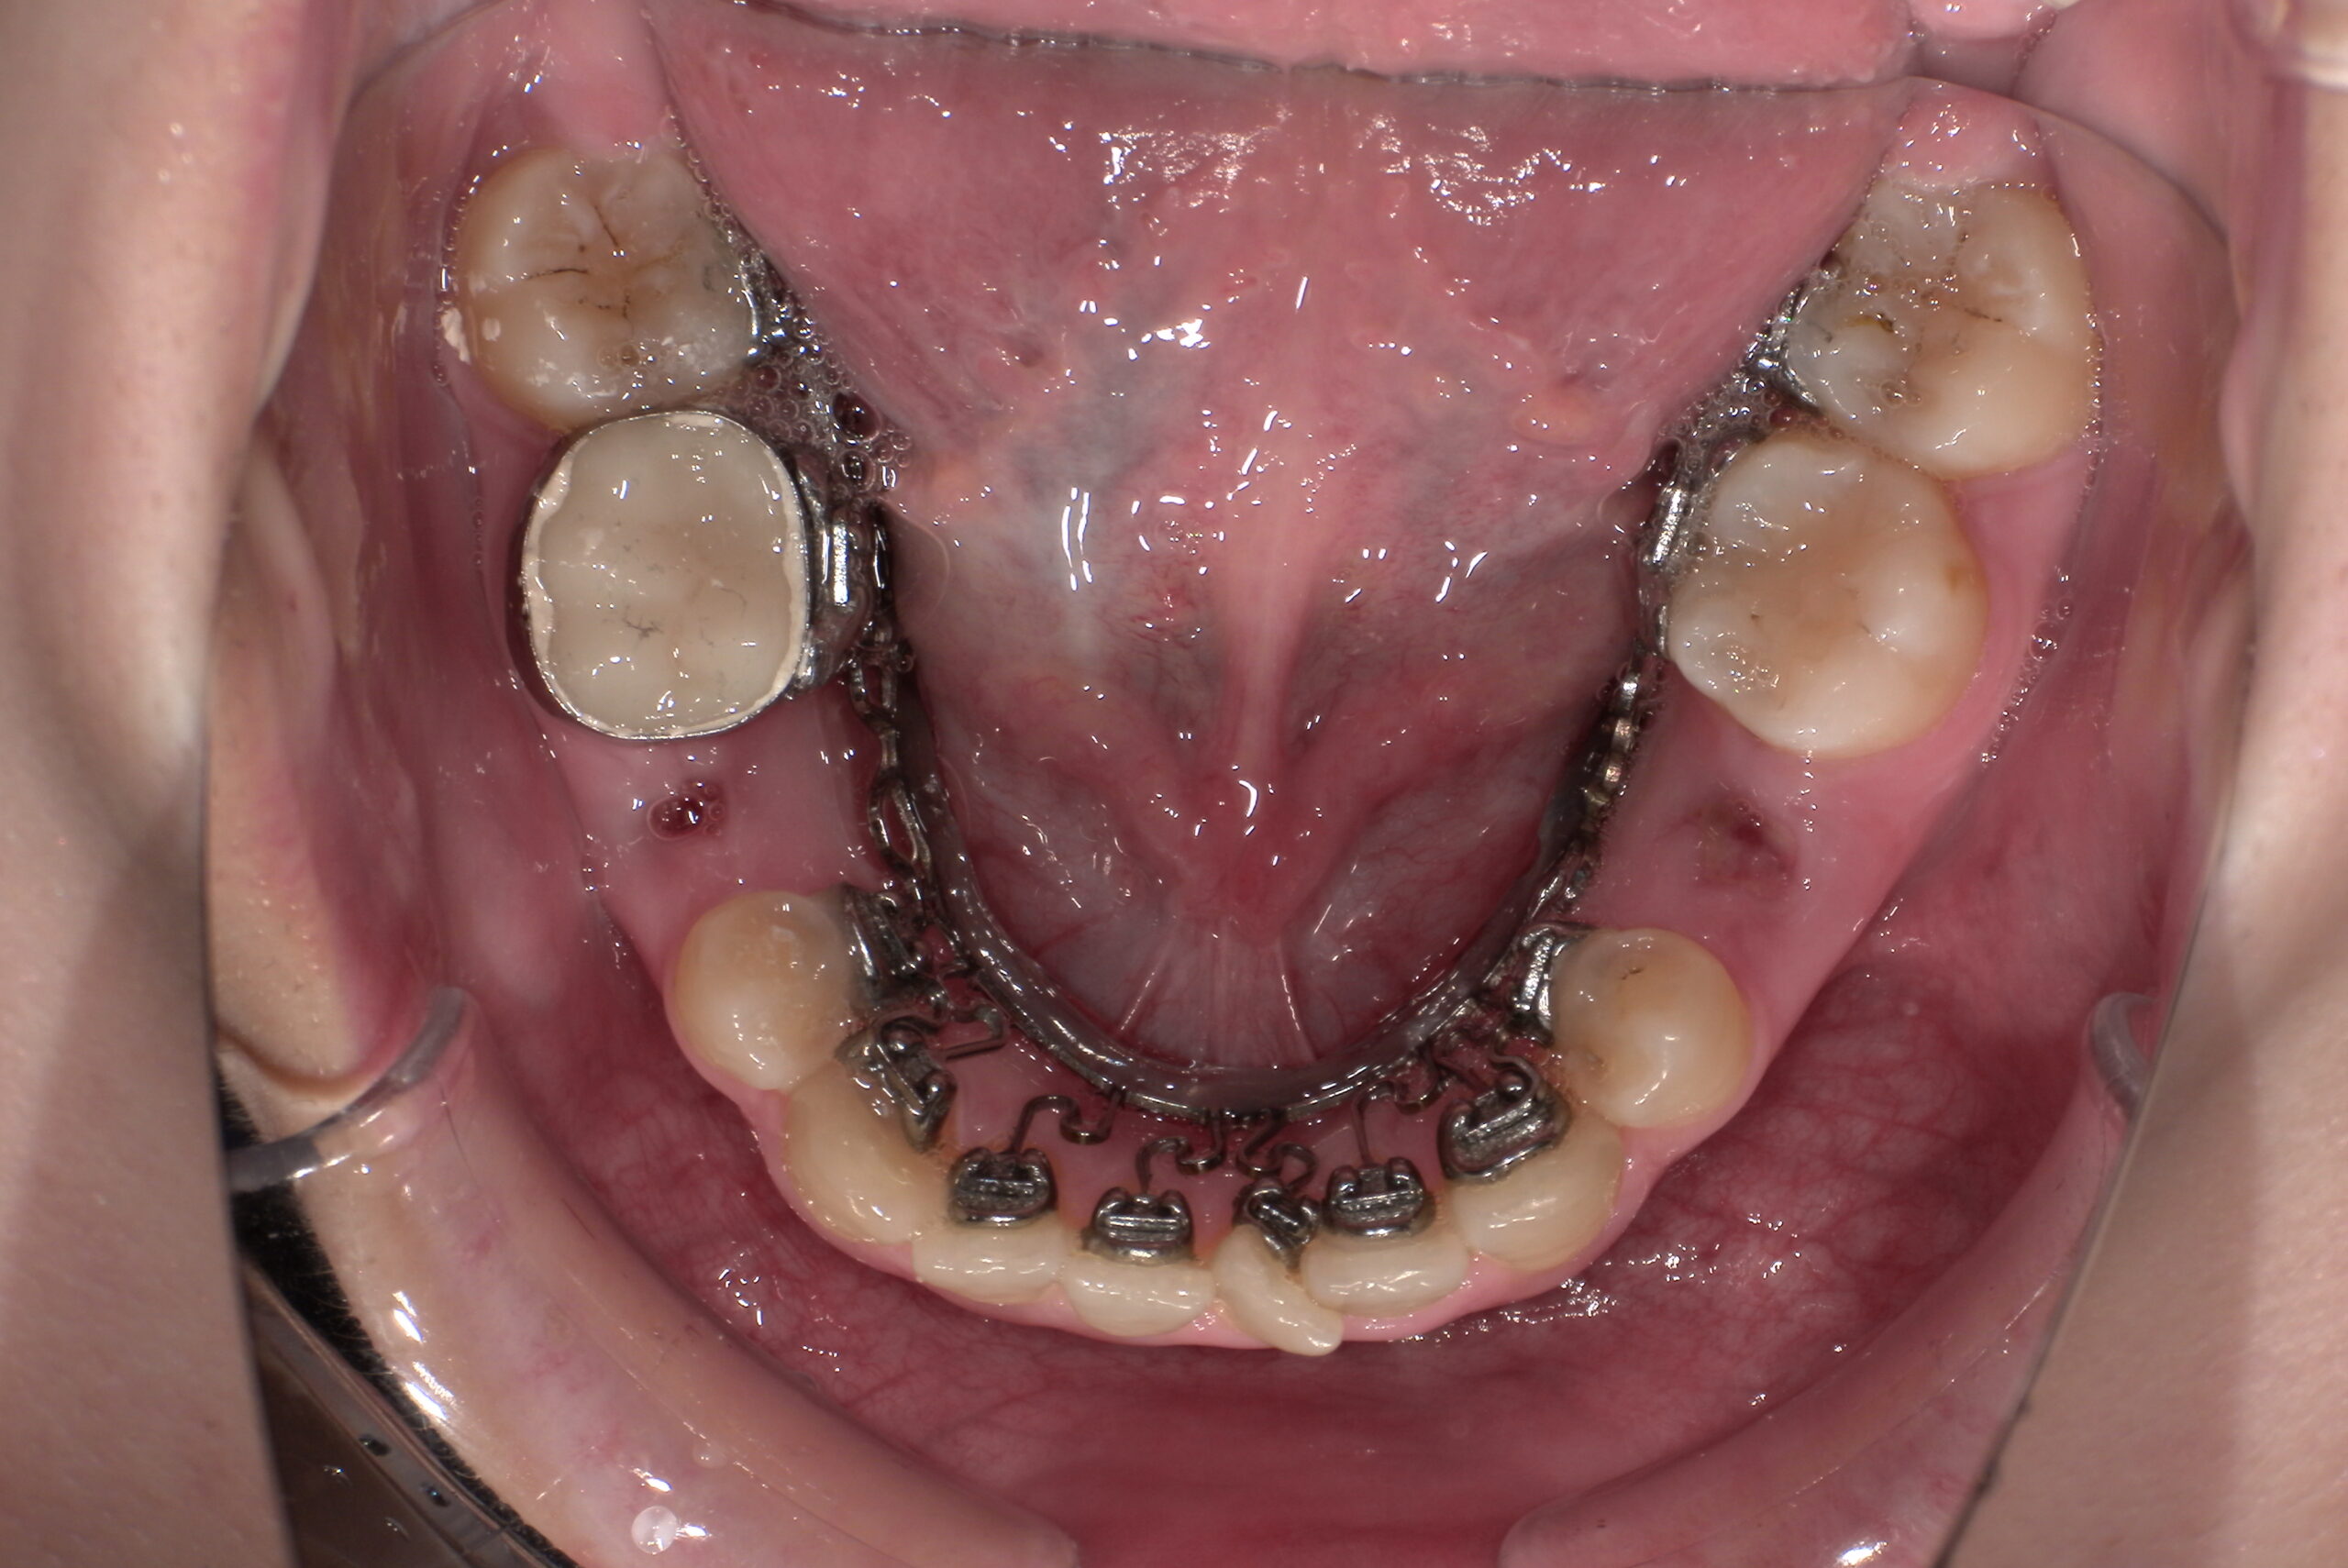

📸治療経過写真

当院で裏側矯正治療しているスタッフの経過写真をご参考にしてください。

上下左右小臼歯を1本ずつ計4本抜歯して現在も治療中です。「歯を抜いた隙間が閉じた量」、「前歯の移動量」、「正面から見た前歯の位置」に注目して見てもらえると、歯の移動の早さが目に見えて分かるかと思います。

約4か月後

(ゴムかけをして奥歯の咬み合わせや出っ歯の治療をするため、何か所かボタンが付いています)

下顎